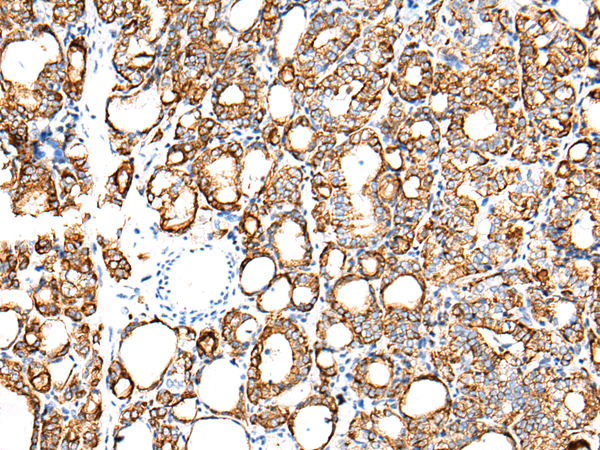

分类: 科研抗体货号: P12452别名: K7; CK7; SCL; K2C7应用: WB,IHC反应种属: Human